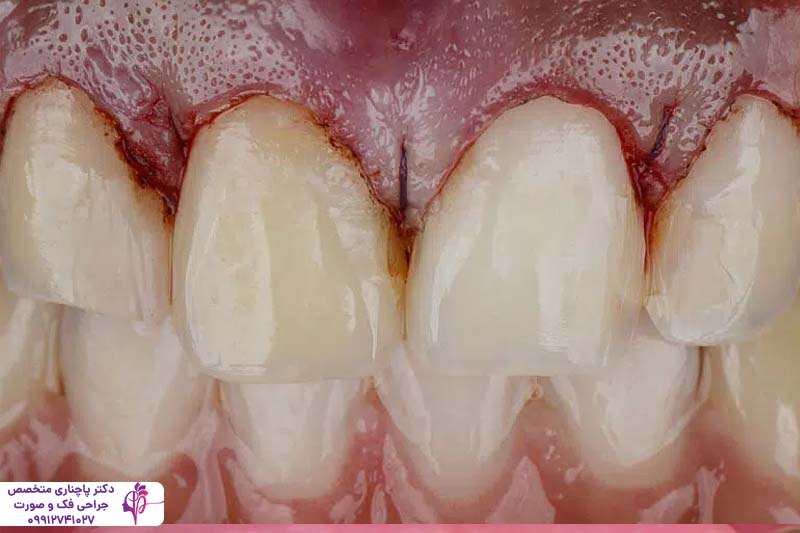

پریودنتیت مرحله پیشرفتهتر و جدیتر بیماری لثه است که در صورت عدم درمان ژنژیویت ایجاد میشود. در این مرحله، عفونت باکتریایی از سطح لثه به بافتهای عمیقتر، از جمله استخوان نفوذ میکند. باکتریها باعث ایجاد کیسههای عفونی یا کیسههای پریودنتال بین دندان و لثه میشوند و به تدریج به عمق بافت لثه نفوذ میکنند و باعث تجمع بیشتر پلاک و جرم میشوند. این مرحله از بیماری پریودنتال به تدریج باعث تخریب بافت لثه و استخوان میشود و در موارد حاد حتی با عقب راندن لثه باعث شل شدن دندانها و رد نهایت افتادن آنها میشود.

این مرحله از بیماری خودش را با خونریزی مداوم لثه، بوی بد دهان و حساسیت شدید دندانها به گرما و سرما و حتی درد در هنگام جویدن نشان میدهد. این مشکل در موارد شدید بافت لثه را کامل از بین میبرد و ریشه دندان نمایان میشود. بر خلاف ژنژیویت این مشکل نیاز به درمان حرفهای از طرف دندانپزشگ دارد. درمان بیماریهای لثه قبل از ایمپلنت در این مرحله شامل تمیز کردن عمیق توسط دندانپزشک، جراحی لثه یا حتی استفاده از آنتیبیوتیکهای قوی میشود. برای بیمارانی که قصد انجام ایمپلنت دارند درمان این مرحله از بیماری لثه قبل از ایمپلنت اهمیت زیادی دارد چون عفونت فعال باعث التهاب در اطراف ایمپلنت میشود و در نتیجه کاشت با شکست مواجه میشود.

روشهای مختلفی برای ترمیم و درمان بیماریهای لثه قبل از ایمپلنت وجود دارد که بسته به شدت بیماری انتخاب میشوند. یکی از رایجترین روشها، تمیز کردن عمیق دندانهاست که شامل اسکالینگ و روت پلنینگ میشود، در این روش پلاک و جرم را از زیر خط لثه برمیدارند تا عفونت کنترل شود. در بعضی موارد پیشرفته و حاد بنا به تشخیص و صلاحدید دندان پزشک جارحی انجام میشود. جراحی فلپ یکی از این روشهای جراحی است که در آن بافت لثه را بلند میکنند تا با دسترسی راحتتر به ریشهها بافت آسیبدیده را بردارند. استفاده از آنتیبیوتیک هم میتواند میزان باکتریها را کم کند.

یکی دیگر از روشهای درمان بیماریهای لثه قبل از ایمپلنت روش گرافت لثه است. در این روش بافت سالم را از جای دیگری برمیدارند و به لثه آسیبدیده پیوند میزنند. لیزر درمانی نیز یک گزینه مدرن است. در این روش به کمک پرتوهای لیزر با دقت بالا باکتریها را از بین میبرند و در نتیجه التهاب کمتر میشود بدون اینکه نیازی به برش دادن لثه باشد. این روش نه تنها به درمان بیماریهای لثه قبل از ایمپلنت کمک میکند بلکه برای حفظ بهداشت دهان و دندان هم موثر است.